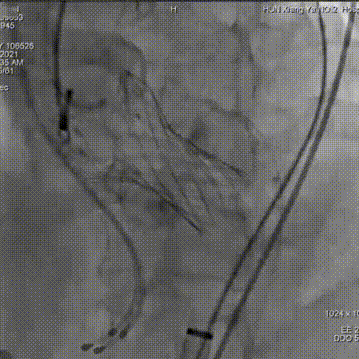

瓣膜工作位释放“烟囱支架”